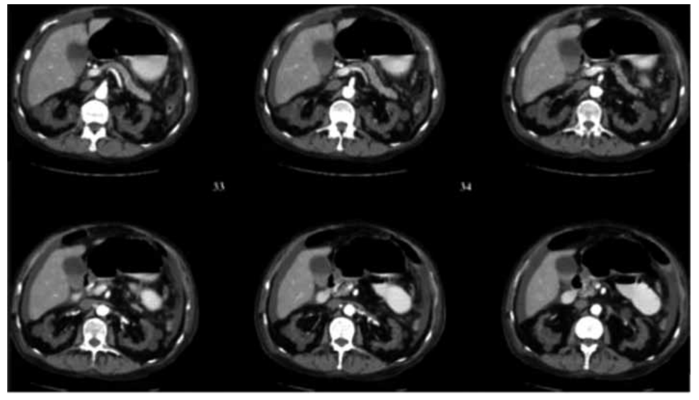

Homem de 72 anos em tratamento dialítico há 8 anos por doença renal crônica de etiologia indeterminada. Refere ter

apresentado um episódio de hematúria macroscópica há 2 dias, associado a dor lombar. Usou analgésico, com melhora

parcial. Tomografia de abdome com imagem a seguir.

O diagnóstico mais provável nesse caso é